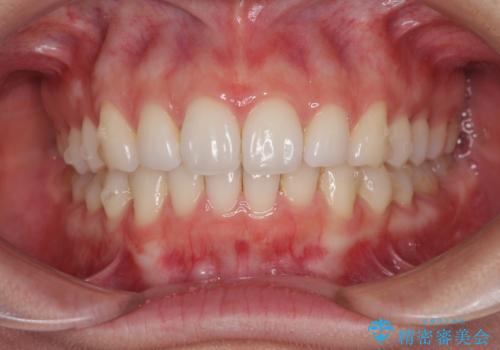

- 上下前歯の叢生を気にして来院された患者様です。

以前矯正をした後戻りということで、歯列不正はそれほど大きくなかったため、インビザライン・ライトを用いて矯正治療を行うこととしました。

前歯のデコボコが残っており、シミュレーション通りに動いていない部分がありましたが、再矯正であることやご本人の満足いくところまでデコボコが改善されたとのことで、治療を終了することとしました。